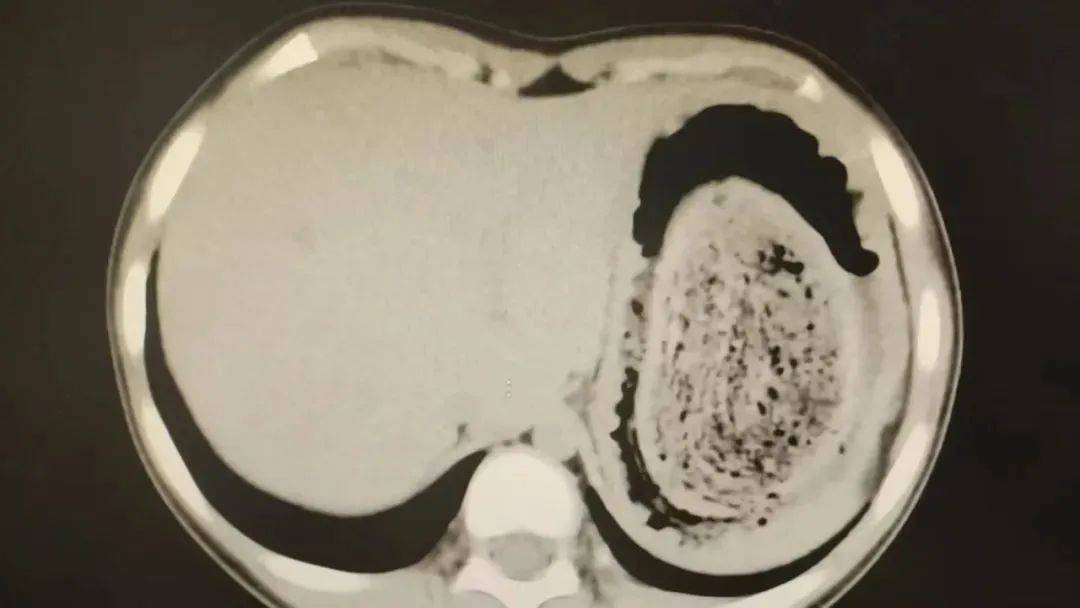

10岁女孩园园(化名)因持续3天的上腹痛伴呕吐被紧急送医皇冠信用网登2。影像学检查结果显示,她的胃部存在一个巨大的团块状阴影,初步怀疑为异物堵塞。据家长回忆,园园从1年前开始就有偷偷吃头发的习惯,但家人并未重视,直到这次症状严重才意识到问题的严重性。